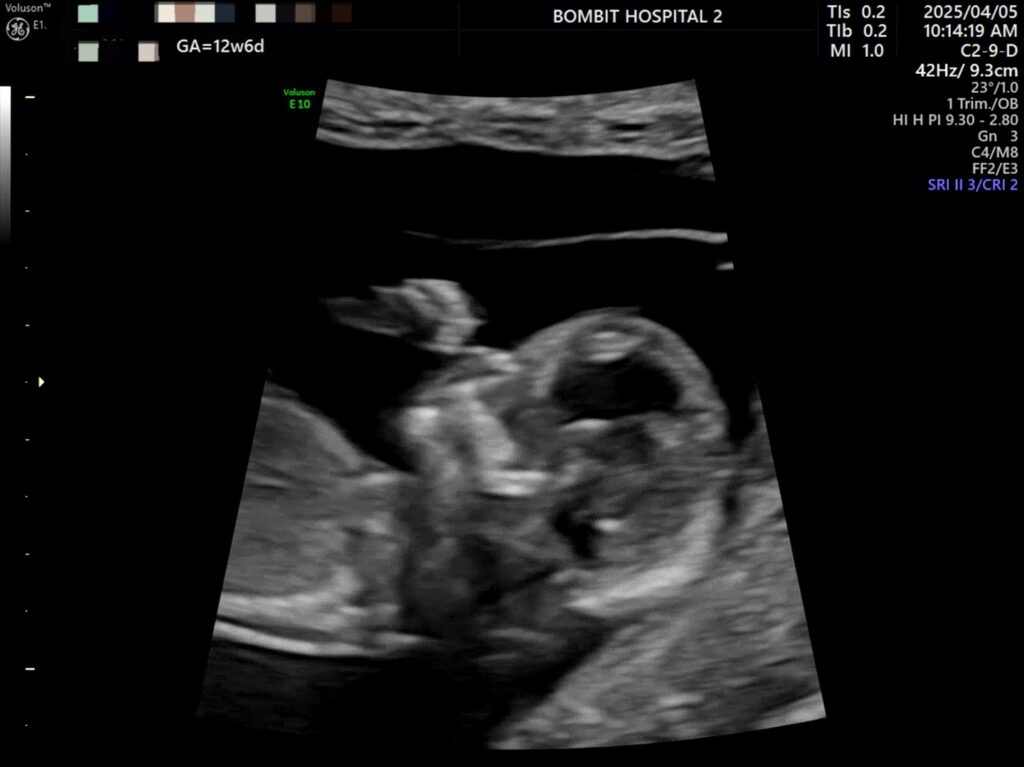

봄빛병원에 다시 방문. 정밀초음파도 하고, 다시 진료도 보았다.

피고임은 이제 없어졌다고 했다. 약간은 느려진 듯한 심장소리도 다시 들었고 니프티 검사용 채혈도 했다.

정밀초음파 사진.